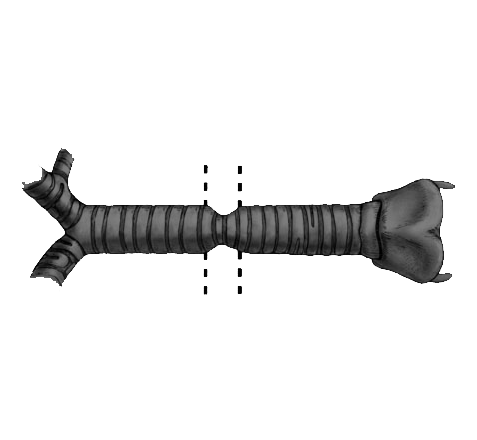

ستێنتکردن لە نەخۆشێکدا کە تەسکبوونەوەی لوولەی هەناسەی هەیە

وۆرک شۆپی پراکتیکی ستێنتکردنی سییەکان

ڤیدیۆی پەروەردەیی21 فروردین 1402